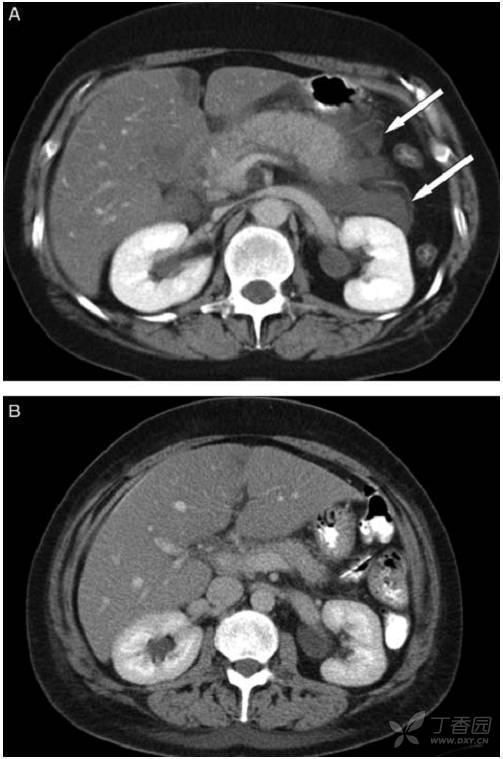

A:38岁,女患,急性间质水肿性胰腺炎,白箭头所示左肾周前间隙急性胰周液体积聚。胰腺完全强化,增大,但由于水肿导致强化不均匀。急性胰周液体积聚呈液体密度,无囊壁包裹。B:几周后,随访CT发现急性胰周液体积聚完全吸收,残留极少胰周脂肪毛糙影。

(2)CT对胰腺炎的严重程度有较大价值

CT-胰腺实质密度增高或降低,体积增大,胰周浸润。

增强CT-清楚显示胰腺坏死区域、范围